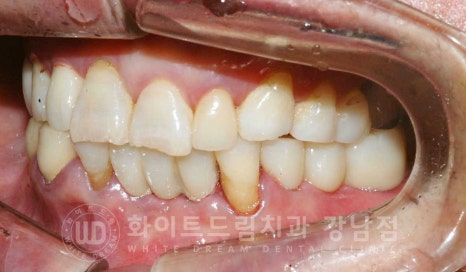

오늘 소개해 드릴 환자분의 초진 사진인데요.

치아가 남아있는 부위는 잇몸뼈가 있고 상실된 치아 부위는 잇몸뼈가 없는 것이 보입니다.

이 부위가 치조골이랍니다.